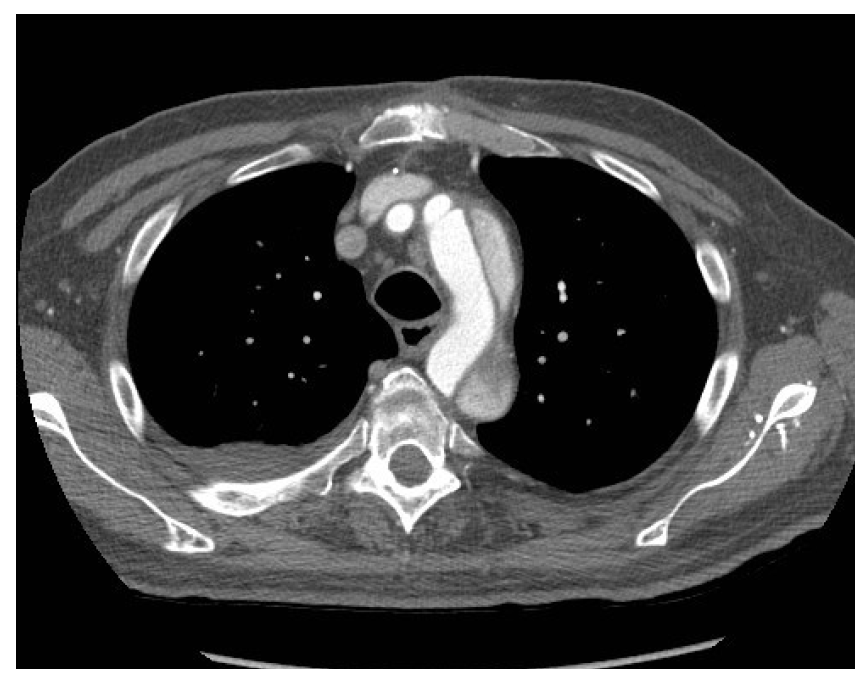

What is this?

aortic dissection